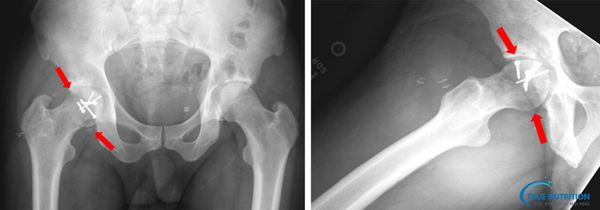

- Lâm sàng: Dựa trên triệu chứng đau khớp háng và hạn chế vận động.

- Cận lâm sàng: Chụp X-quang, MRI hoặc CT scan để xác định mức độ tổn thương của chỏm xương đùi.